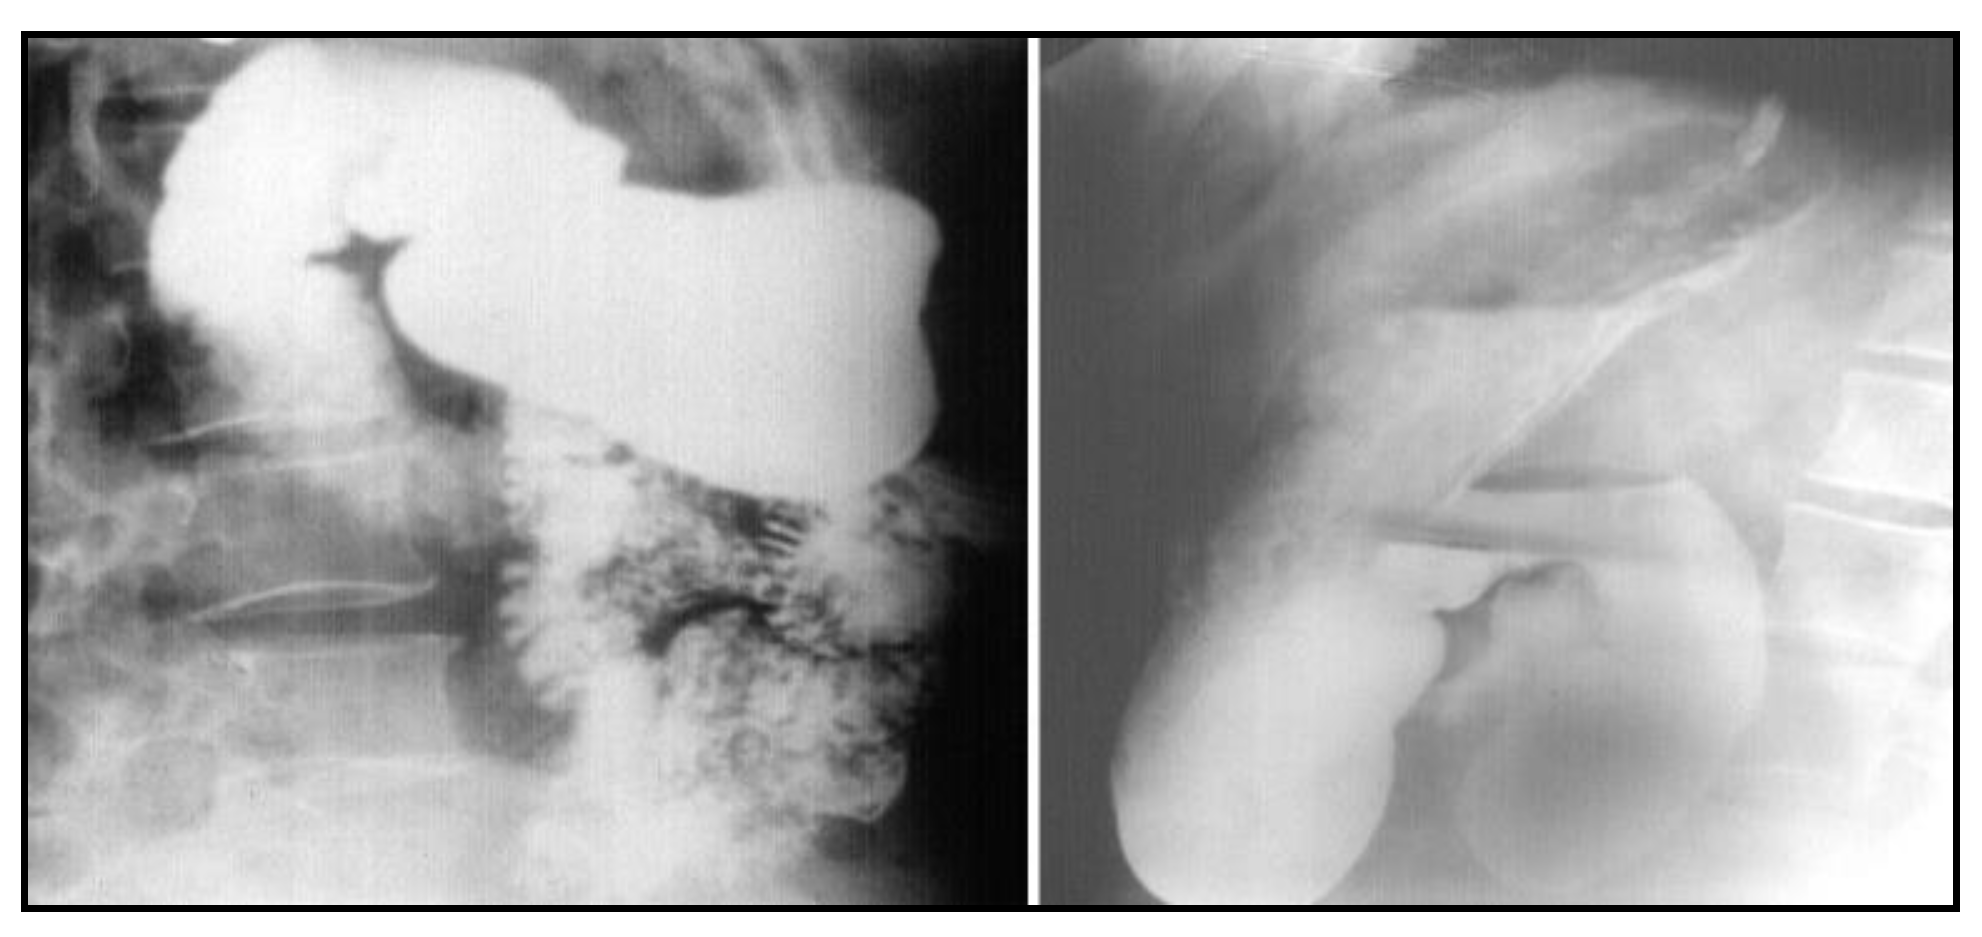

After nasogastric tube positioning, the upper endoscopy revealed dilated hypotonic stomach and duodenum with lesions of erosive gastritis and duodenitis. Using barium study of the upper gastrointestinal tract, we found a filling defect of the fourth portion of the duodenum, with dilated stomach and duodenum proximal to the site of obstruction; we also found gastroesophageal reflux without radiological signs of hiatal hernia (Figure 1). Ultrasonography and CT scan showed no metastases.

Figure 1. Barium study of the upper gastrointestinal tract filling defect of the fourth portion of the duodenum with dilated stomach and duodenum proximal to the site of obstruction and gastroesophageal reflux without radiological signs of hiatal hernia.

Figure 7. Follow-up barium study of the upper gastrointestinal tract widely patent anastomosis with a normal mucosal pattern between the proximal duodenum and jejunum.